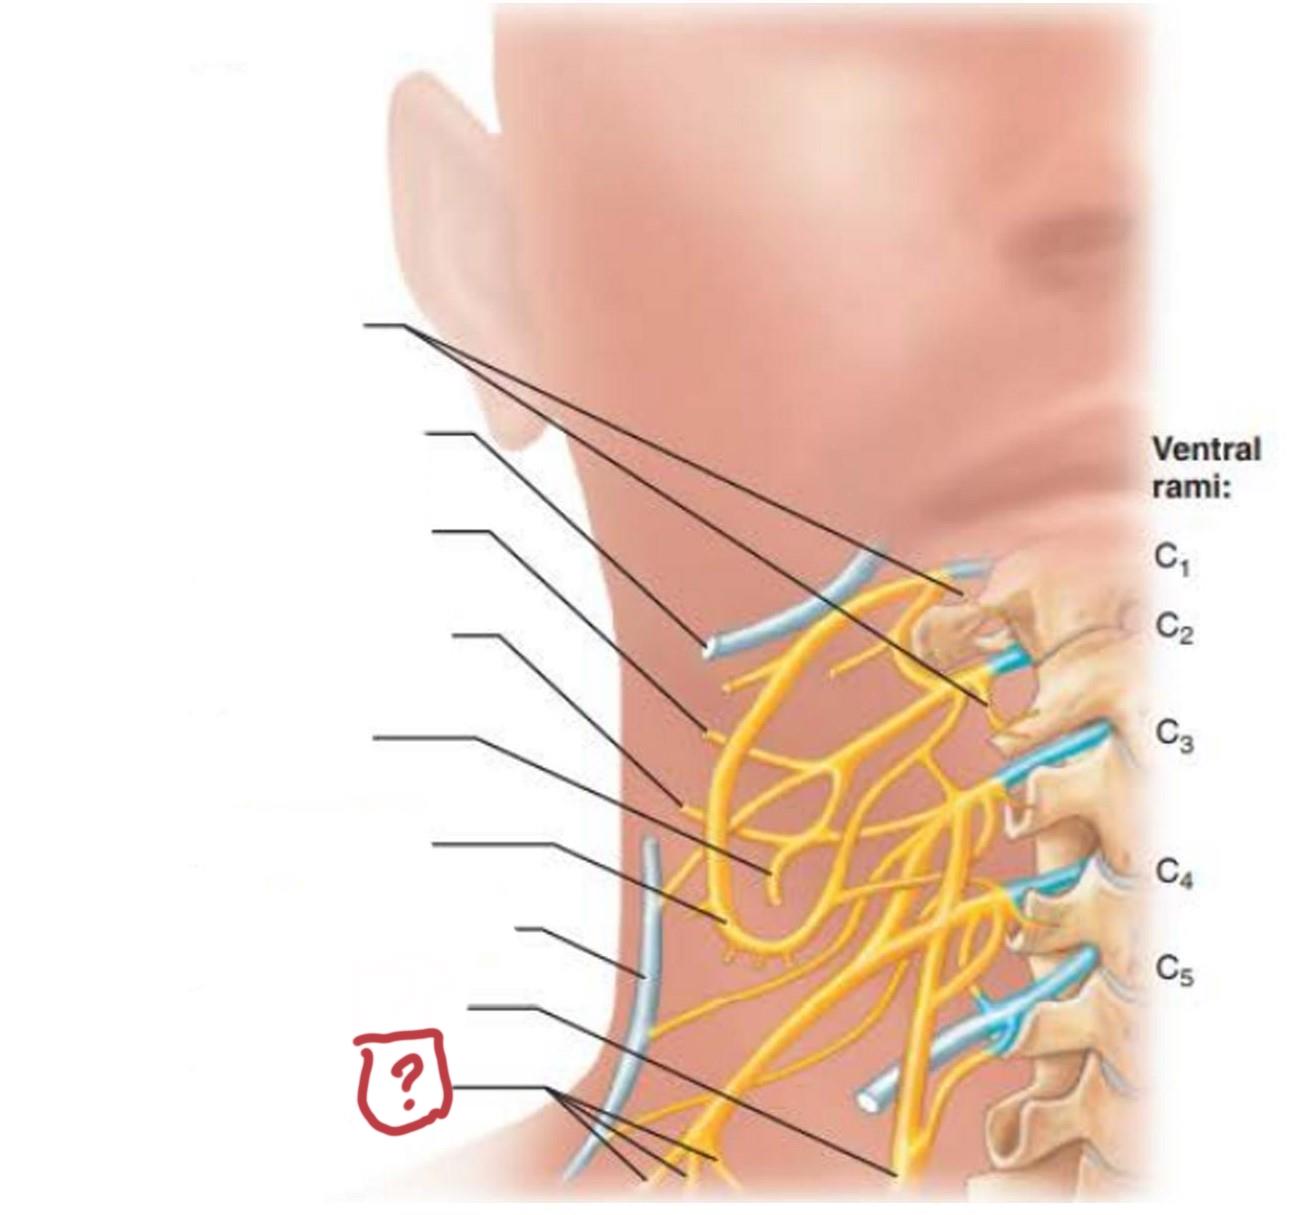

cervical plexus

C1-C4

segmental branches

hypoglossal nerve (12)

lesser occipital nerve

greater auricular nerve

transverse cervical nerve

ansa cervicalis

accessory nerve (11)

phrenic nerve

supraclavicular nerves